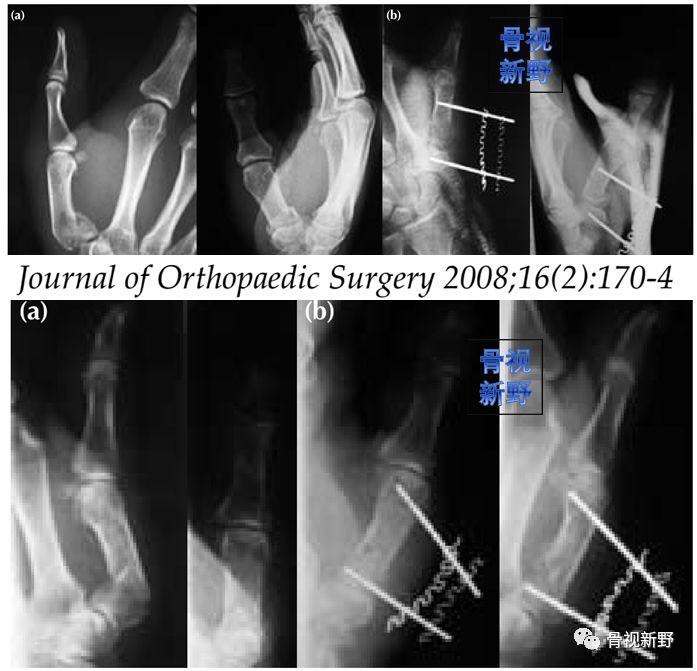

case1

case 2

经皮双针交锁固定可防止退针、维持骨折的复位及拇指的外展对掌位。